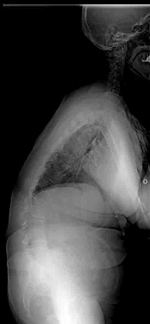

せぼね(脊椎)は7個の頚椎、12個の胸椎、5個の腰椎と仙椎から構成されます。正常な状態では脊椎は正面から見ると真っ直ぐです。一方側弯症では正面から見た時に椎体がねじれ(回旋)を伴いながら、脊椎が左右に曲がっている状態です。側弯症の発生頻度は、装具治療の対象となる20-30度以上の側弯症はおおよそ0.3~0.5%と報告されています。手術が必要な可能性が出てくる40度以上の側弯はおおよそ0.1%です。

手術の最大の目的は側弯の進行の予防です。進行の確率は、10~12歳の場合、コブ角30度以上の側弯では約90%の確率で、コブ角60度以上の側弯の場合は100%の確率で進行します。仮に重度の側弯症になった場合、疼痛や整容的な問題にとどまらず、肺機能の低下(息切れ)が生じます。これは脊柱の変形によって肺が圧迫されるためです。骨の成長終了後(18-20歳以上)もコブ角が40度を超えた側弯症は年間0.5~1度程度の進行があるといわれております。成長終了後の側弯症では、今後の側弯の進行の可能性と手術の危険性などを主治医と相談して、手術を受けるかどうか決めたほうが良いと考えられています。

おとなの側弯症には主にせぼねの加齢による変形が原因となる変性側弯症と子供の頃からせぼねの変形があり、成人後に進行した特発性側弯症の成人期遺残があります。変性側弯症と症状は腰痛から始まることが多いのですが、変形した組織が神経を圧迫すると下肢の痛みや筋力低下などの神経症状が進行することもあります。特発性側弯症の成人期遺残では症状は全くない場合もありますが、軽度の腰痛や背中の痛みがある場合が多いです。いずれの側弯症でも変形が進行すると体幹のバランスを保てなくなり、杖などの支えが必要な状態となります。